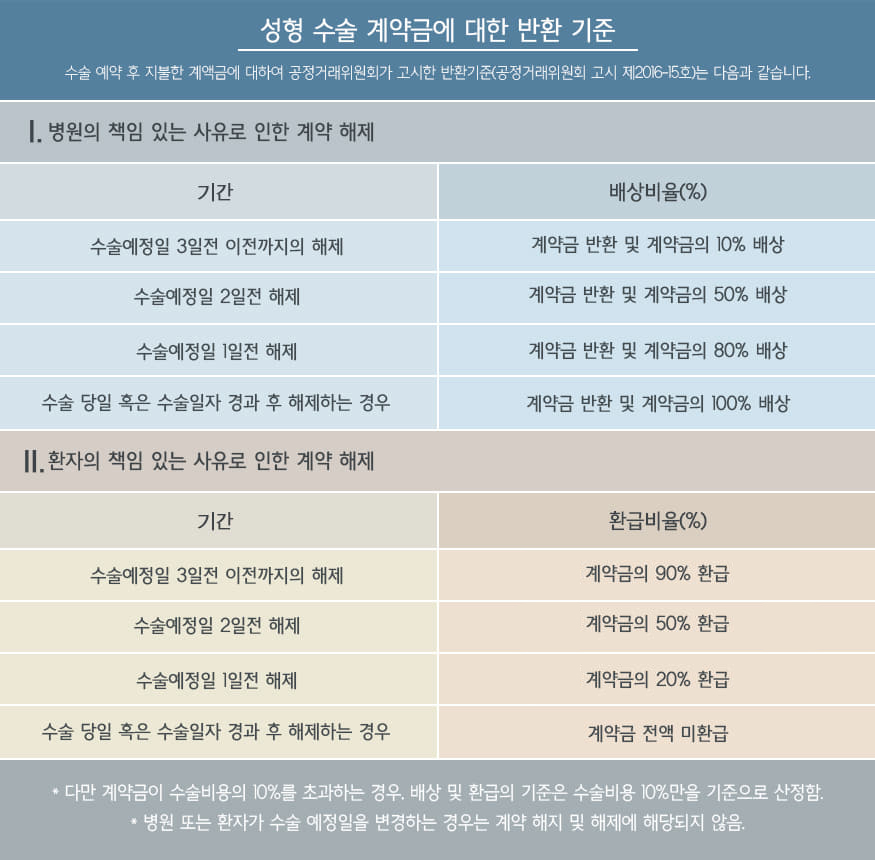

비염의 진단과 결과

정확한 원인파악을 위한 삼성드림이비인후과의 진단

CT

CT

세계적으로 인정받는

Amorphous Silicon Flat Panel

센서를 사용하여 선명한 고화질로

환자의 상태를 볼 수 있어

정확한 진단이 가능한 CT로 진단

세계적으로 인정받는

Amorphous Silicon Flat Panel

센서를 사용하여 선명한 고화질로

환자의 상태를 볼 수 있어

정확한 진단이 가능한 CT로 진단